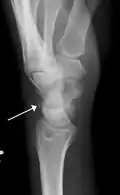

Triquetral fractures can occur due to forceful flexion of the wrist, causing an avulsion of the dorsal aspect of the bone that is often hidden on anterior radiographs, but can be seen as a tiny bone fragment on lateral views.

- Triquetral fracture indicated by the white arrow.

- Triquetral fracture as seen on lateral view of a radiograph.